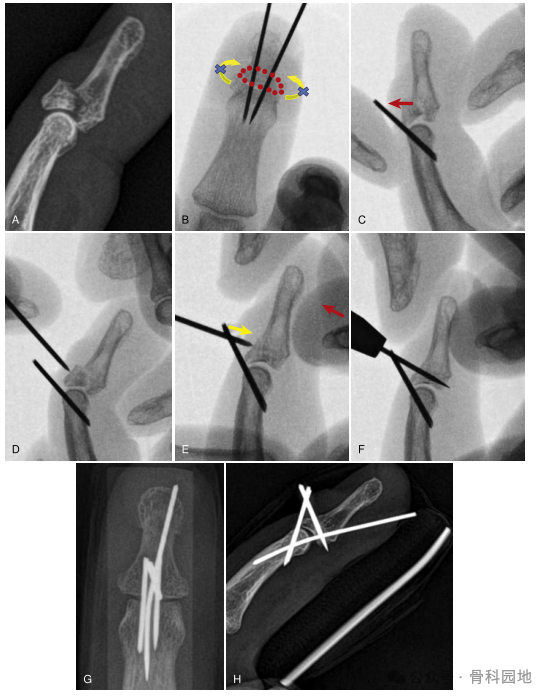

6、骨折碎片超过关节面50%时,采用改进的双延伸块技术(延伸块技术复位不可复位锤状指骨折的补充方法:背侧反力技术,中华手外科杂志,2018年11月5日。)

注:B,两条平行的块线相距2mm插入。注意两根平行的挡丝防止背片在轴向面旋转(黄色箭头)。红色圆圈,背部骨块。C,牵引和背侧平移闭合复位。D,使用1.1 mm克氏针对背部骨块施加力。E,黄色箭头表示克氏针对背侧的反作用力。F-H,固定。